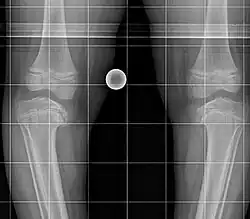

Röntgenbild eines Mädchens mit beidseitigem Morbus Blount rechts Stadium V und links Stadium IV

Nach Langeskjöld[2] können verschiedene prognose- und therapierelevante Stadien unterschieden werden:

• Stadium IV: Verschmälerung der Wachstumsfuge mit deutlicher Schrägstellung

• Stadium V: Zusätzliches Deformierung und Teilung der Epiphyse

• Stadium VI: Brückenbildung zwischen Epi- und Metaphyse auch mit teilweiser Fusion der fragmentierten Epiphyse an die Metaphyse medial.